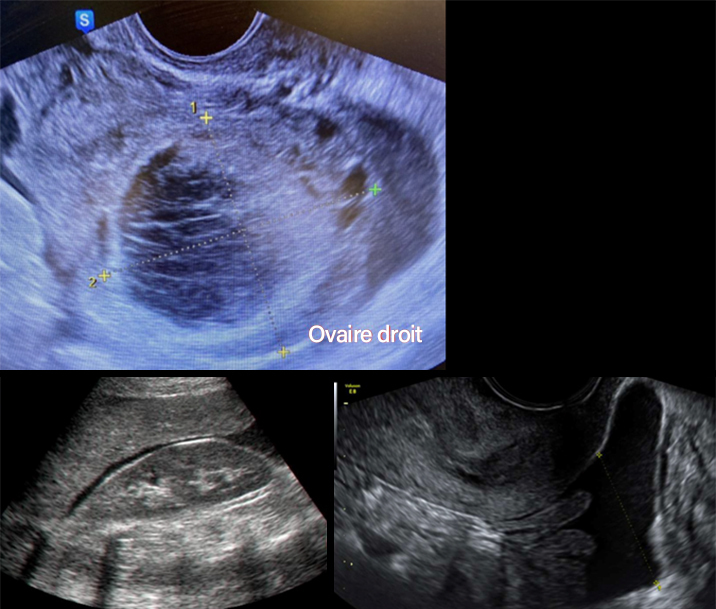

L’échographie objective l’image suivante (fig. 3) de 60 mm de grand axe au niveau de l’ovaire droit.

Figure 3 (Rodolphe Matias de Sousa, La Revue du Praticien)

Question 5 - Qu’en pensez-vous (une ou plusieurs réponses exactes) ?

Vous êtes devant un tableau typique de kyste fonctionnel. Il faut contrôler sa disparition à trois mois. Si le kyste persiste il faudra discuter d’une kystectomie. On peut proposer une contraception œstroprogestative en continu afin de bloquer l’ovulation en attendant.

Il n’y a pas de vascularisation périphérique anarchique sur cette image. Le gros vaisseau prenant le signal Doppler correspond à l’artère iliaque interne.

On ne réalise une IRM pelvienne qu’en cas de kyste suspect de malignité ou organique. Il n’est pas recommandé d’en réaliser une pour un kyste uniloculaire fonctionnel inférieur à 70 mm. Les marqueurs à prélever en cas de lésion suspecte sont : CA 125, CA 19-9, ACE.